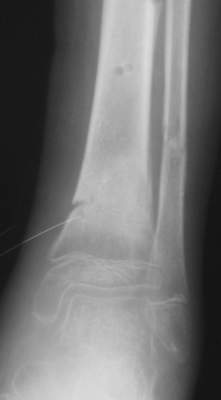

A>> Скелетное вытяжение за пяточную кость.

AVM> А на вытяжении и в гипсповязке в течение 4 мес варуса видно не было?

Так как речь зашла непосредственно о травме, см этапные

снимки. Как все было

Вытяжение